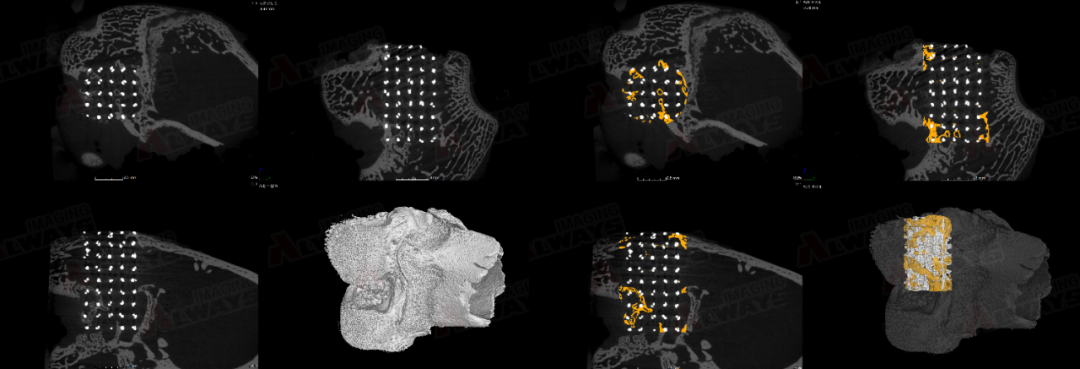

兔子顱骨殘缺成骨

圖片